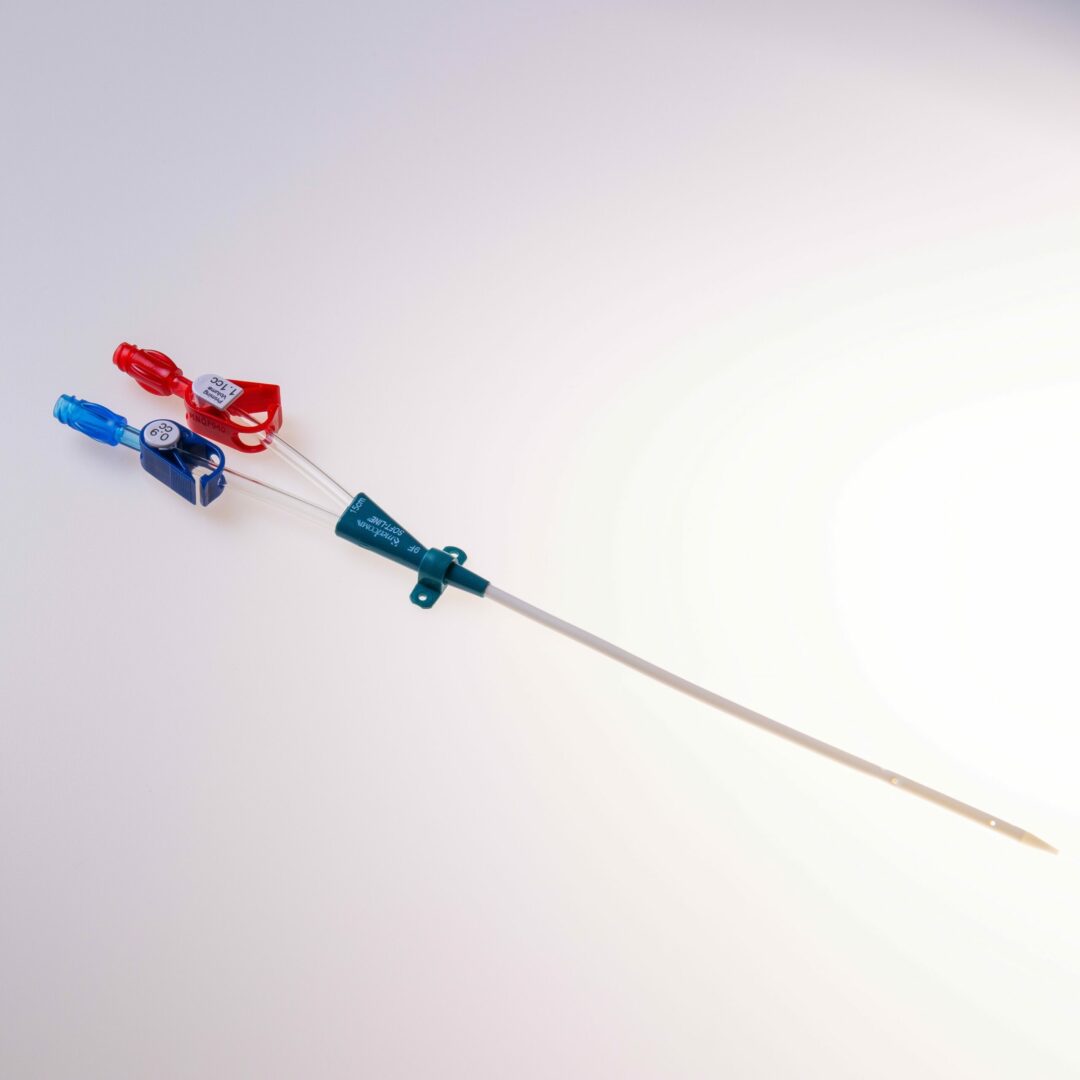

Tip Design

Der Softline® verfügt über ein konisches Spitzendesign und weist einen Lumendurchmesser von 7 French oder 9 French auf.

Produktbeschreibung

Der Softline® erfüllt eine wichtige Überbrückungsfunktion, indem er als temporäre Lösung dient, bis ein möglicher permanenter Zugang etabliert und einsatzbereit ist oder bis zur erfolgten Nierentransplantation. Dieser Katheter ist speziell entwickelt, um den Anforderungen pädiatrischer Patienten gerecht zu werden und ihnen eine optimale Behandlung zu ermöglichen.

Die Einführung in das Gefäß erfolgt über den Führungsdraht.